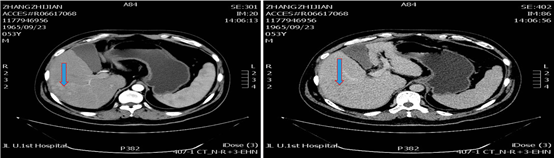

于2019年10月10日复查,检查肝增强CT示,肝脏多发占位性病变,考虑原发性肝癌,部分病变为TACE治疗后改变,其内可见肿瘤存活,对比2019年8月17日病变增多增大,碘油沉积增多。再次DSA引导下行TACE治疗。

图片

图:肝增强CT(2019-10-10)

2020年4月8日复查,异常凝血酶原7793.7 ng/ml;肝增强CT提示,肝脏多发占位性病变,考虑原发性肝癌,可见肿瘤存活,对比2019年10月10日病变增多增大。

图:肝增强CT(2020-4-8)